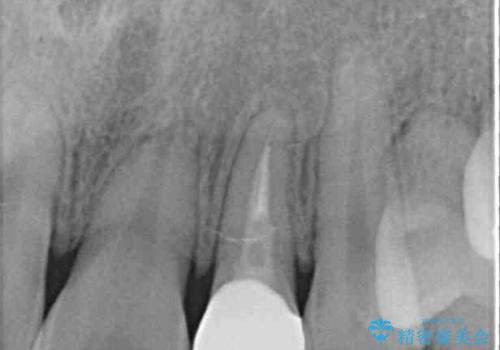

- 下顎の歯が舌側に倒れていることと、前歯の咬み合わせの不具合を気にして来院された患者様です。

受け口傾向の口元であるため、下顎左右小臼歯各1歯を抜歯して歯列を整えることとしました。

前歯には治療中の仮歯が装着されていたため、矯正治療後にオールセラミッククラウンにて補綴治療を行うこととしました。